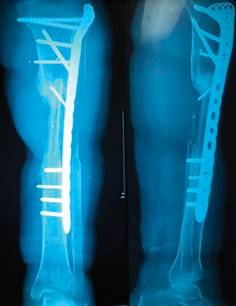

Segunda reintervención: la presencia de la fractura de consolidación motivó la realización de curetaje y reubicación del injerto de peroné proximal con protección de placa LCP tibia proximal (Figura 7).

Figura 7: Resultado de reintervención de osteosíntesis de fractura de consolidación proximal con placa LCP tibia proximal.